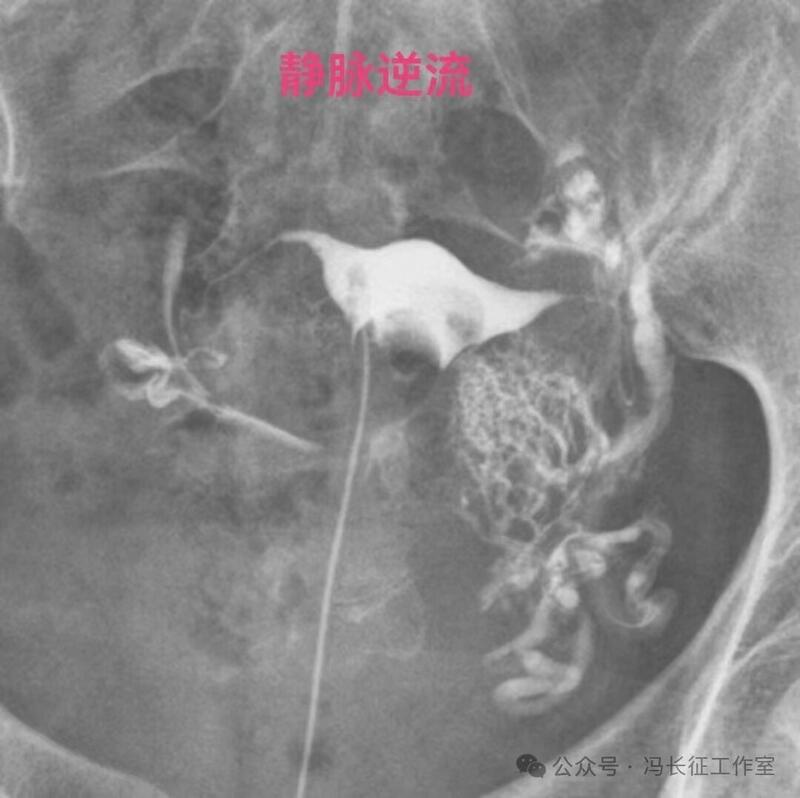

在子宫输卵管造影,用碘油做造影剂当出现逆流时立即停止造影检查,避免更多碘油进入静脉造成肺栓塞是正确的。但是,当用的造影剂是碘水时,出现逆流时还是可以继续进行造影检查,最终完成造影检查,尽量给被检查者一个完整的检查。千万不要听所谓的砖家乱讲,当发现有造影剂进入间质或血管,应立即停止造影。我们大家都知道成人在做CT增强检查时,常规用高压注射器直接从静脉注入约100毫升含碘水剂进行检查几十年了,因此,碘水是可以进入静脉和淋巴的。一般子宫输卵管造影所用含碘水剂20毫升左右,即使20毫升含碘水剂都逆流静脉不会对身体有啥影响的。因为含碘水剂主要经肾从尿液排出体外,有时还相当于免费送一个静脉肾盂造影检查。

造影剂逆流可以进入静脉和淋巴管,逆流分三种:(1)淋巴逆流;(2)静脉逆流;(3)淋巴和静脉混合性逆流。其实,一般多是静脉和淋巴都有的混合性逆流,淋巴逆流是造影当时以淋巴逆流为主,同时有少量的静脉逆流,本来淋巴管后来就是要汇入到静脉的。静脉逆流也是以静脉逆流为主,同时有少量的淋巴逆流。